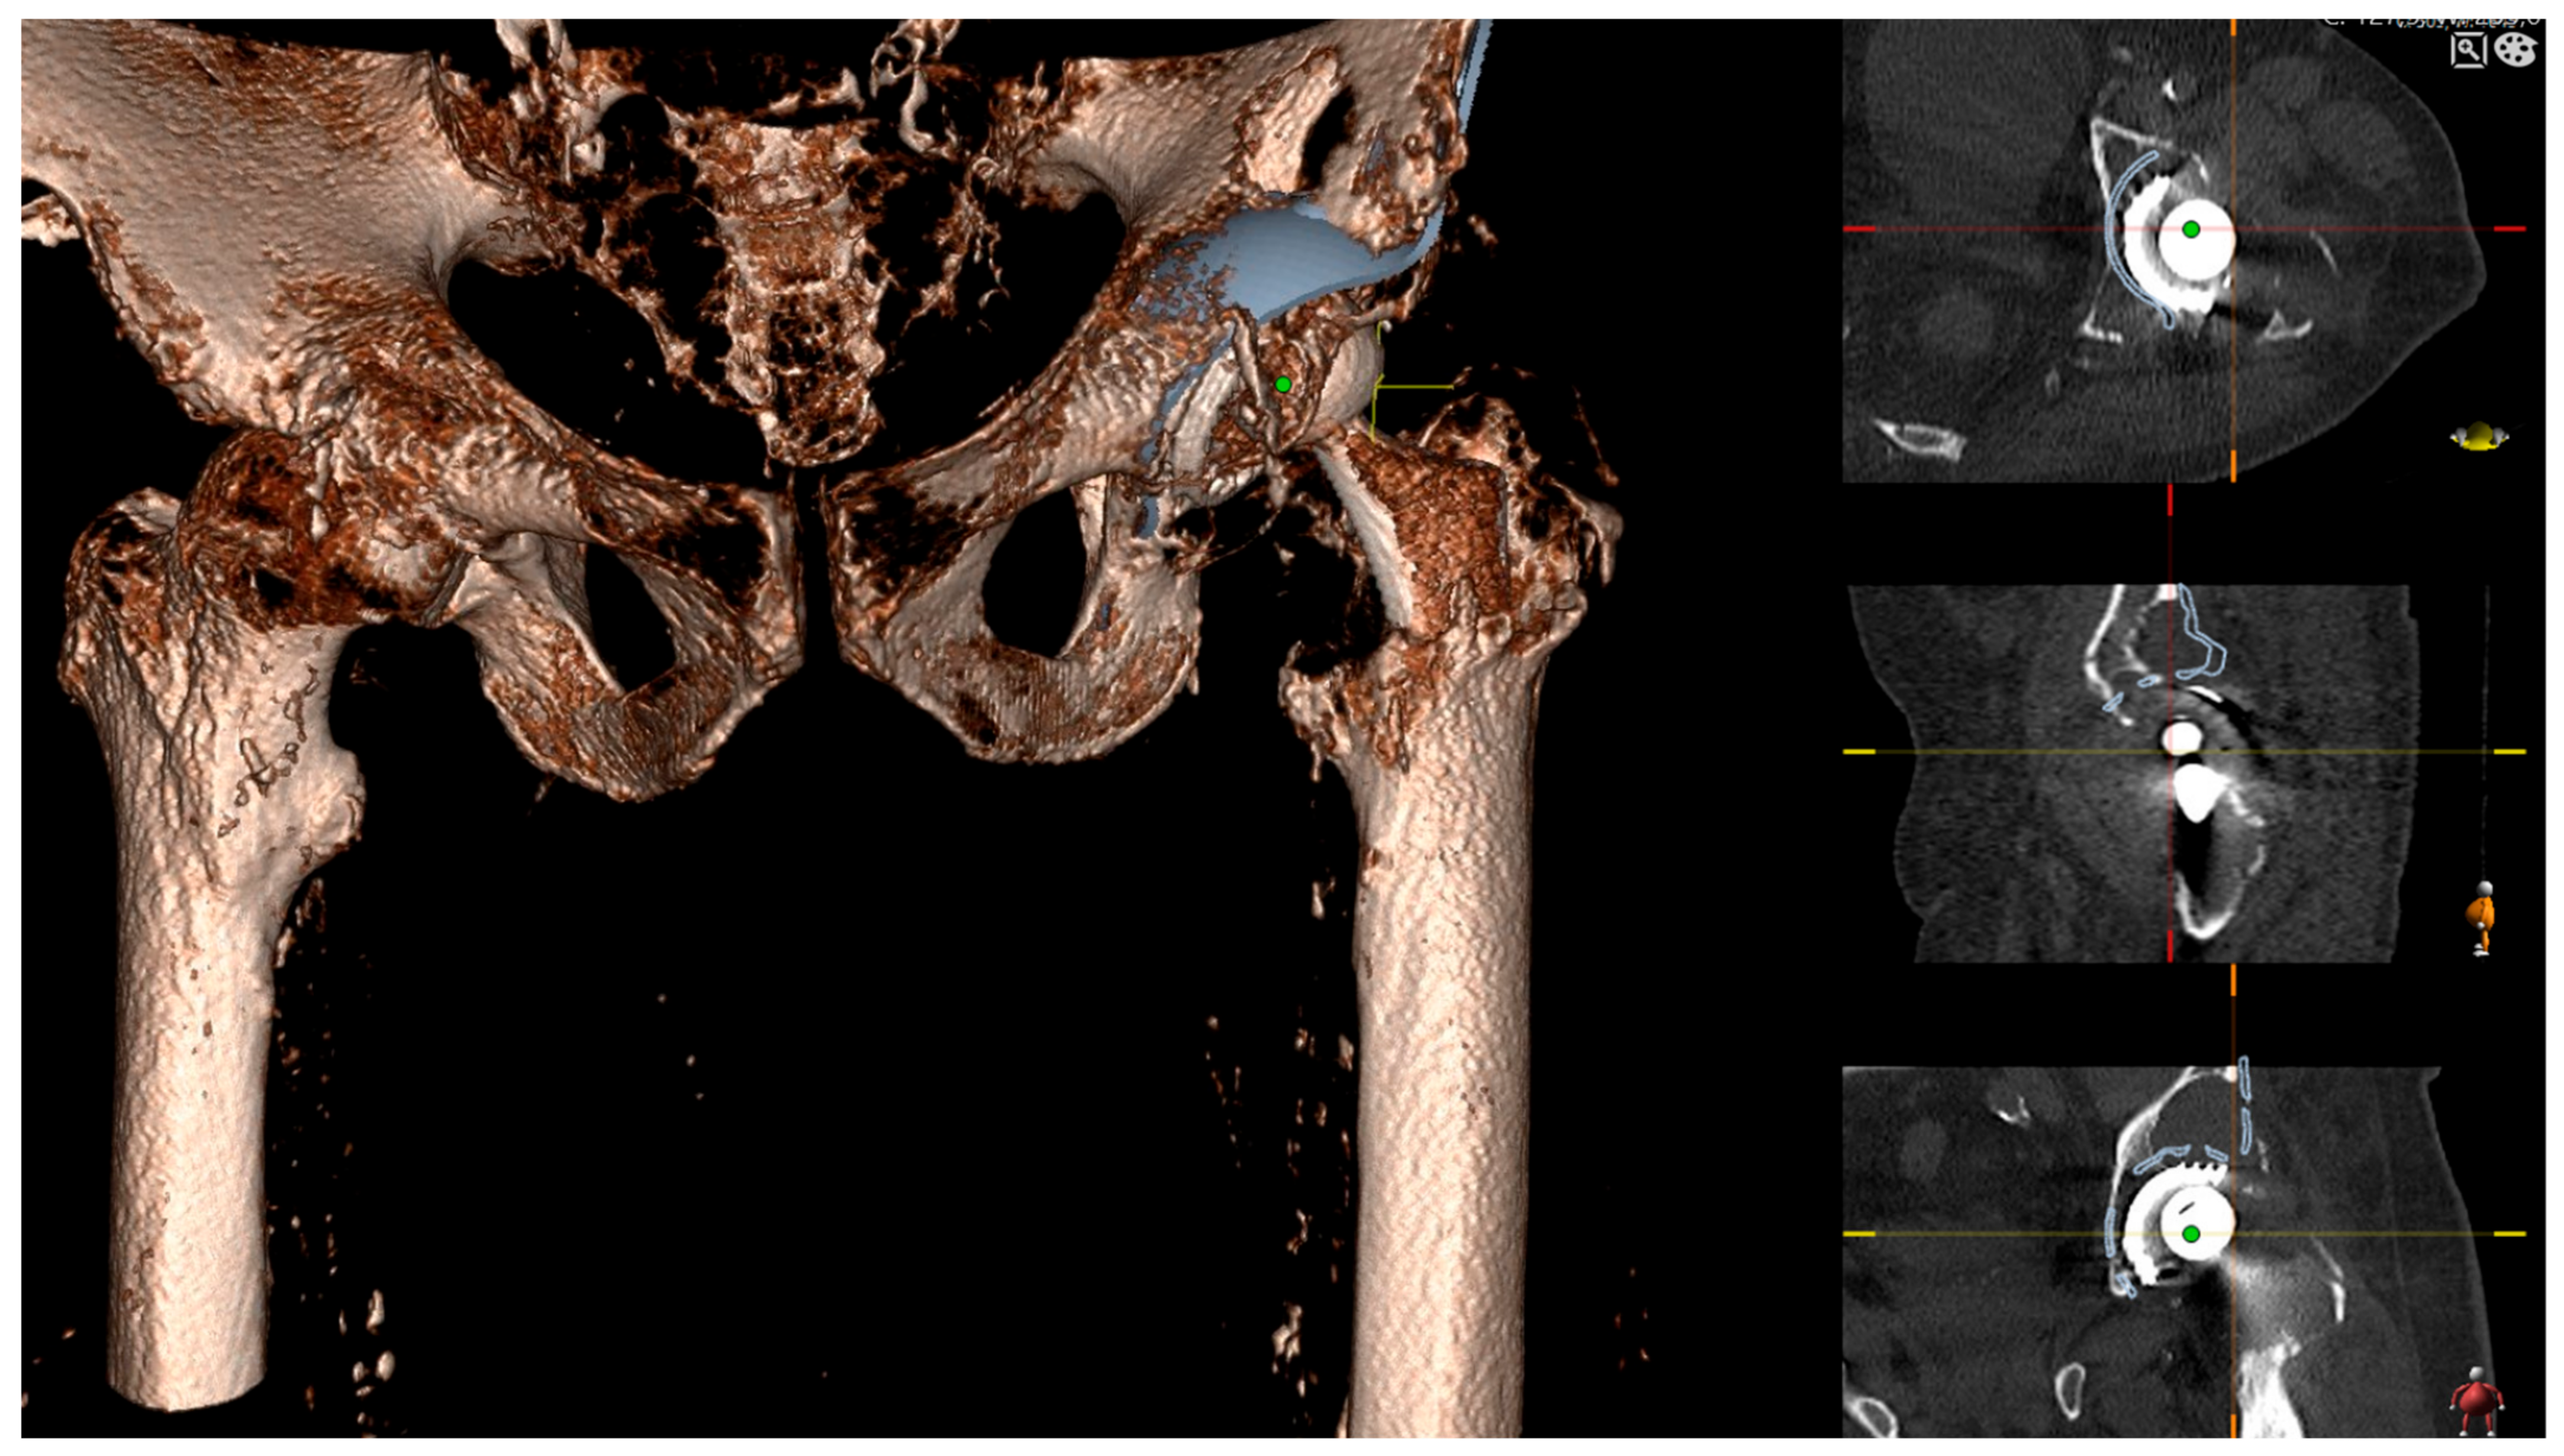

2.1. Preoperative Imaging

2.2. Digital Templating